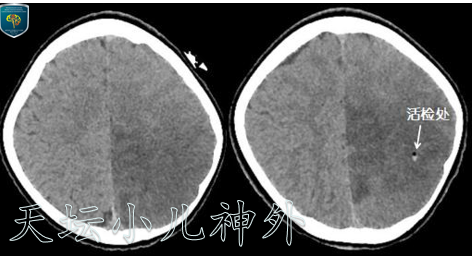

为明确诊断,于2020年7月22日在外院局麻下行立体定向活检术,病理回报示:神经胶质纤维背景中弥漫不均匀分布小圆细胞,细胞形态温和,结合免疫组化,不除外混合性神经元胶质肿瘤。该病理诊断仍较为模糊,无法指导后续治疗。

图3立体定向活检前后CT